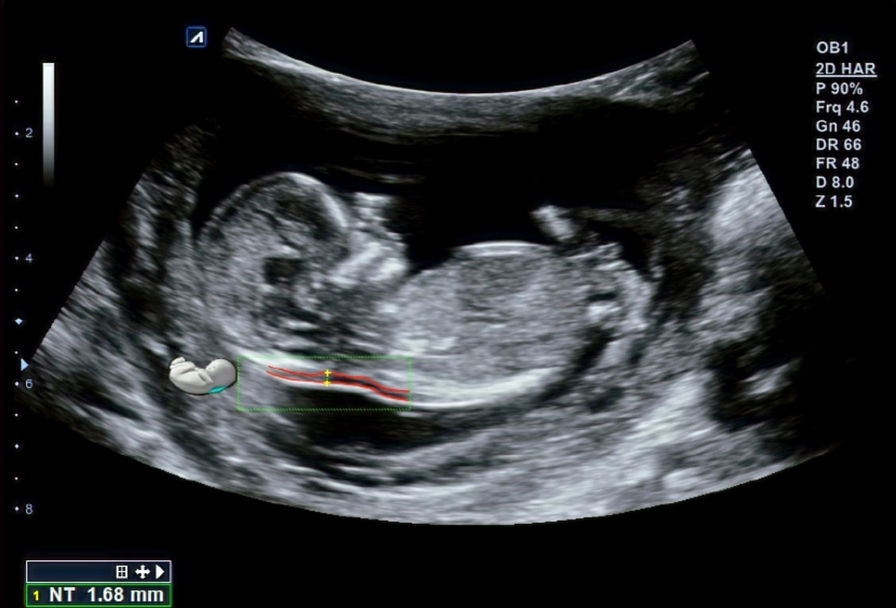

ECOGRAFÍA DE LAS 12 SEMANAS

El examen de semana 12 es el estudio ecográfico más importante del primer trimestre que puede ser realizado entre 11 semanas + 4 días y las 14 semanas + 1 día o para ser más preciso cuando el feto tiene una longitud craneocaudal máxima entre 45 y 84 mm. Este estudio aporta importante información, se realiza habitualmente a través del abdomen materno y frecuentemente se agrega la vía transvaginal según necesidad.

La ecografía de las 12 semanas permite comprobar el grosor del pliegue nucal (Translucencia nucal) que junto con los resultados de los marcadores bioquímicos (niveles de dos proteínas fabricadas por la placenta), la edad materna y las semanas de gestación ofrecen un cálculo del riesgo de alteraciones cromosómicas en el feto.

La TN es un marcador de síndrome de Down, esta medición se une actualmente a otros marcadores ecográficos de menor peso, como la presencia o no de huesecillos nasales (si en la semana 12 del embarazo no se están formando los huesitos de la nariz del bebé, hay un mayor riesgo de Síndrome de Down).